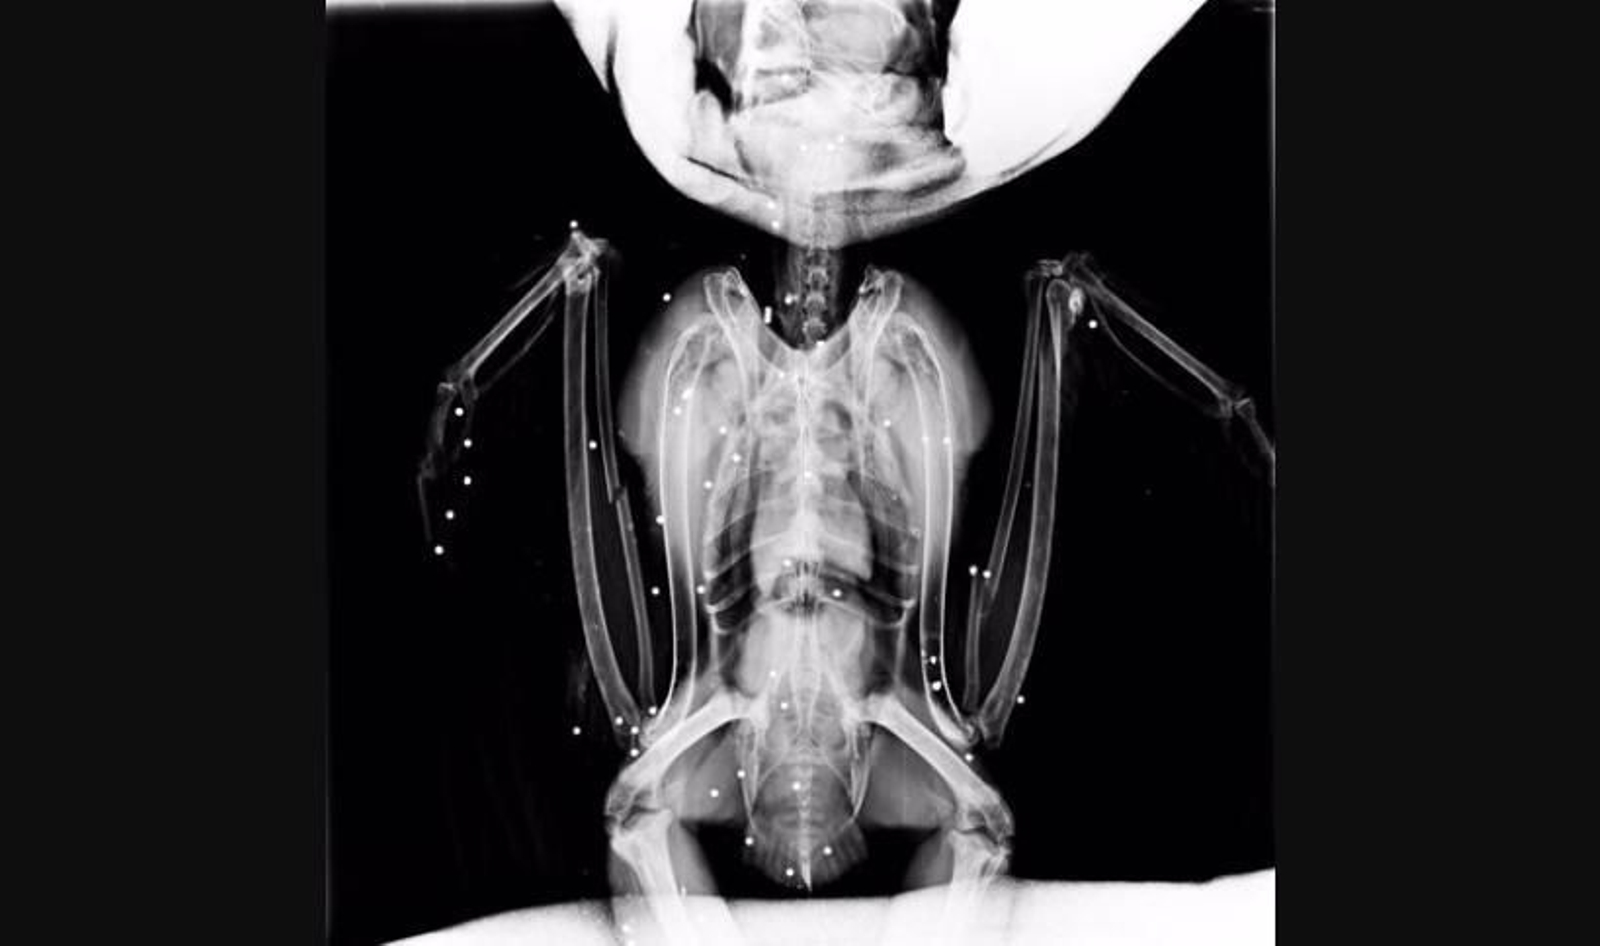

Respecto al búho real, han señalado que fue rescatado por los efectivos de los Agentes Forestales en Villarejo de Salvanés el 4 de febrero, y que el ave presentaba "igualmente una gran cantidad de lesiones", en este caso producidas por los "más de 40 perdigones recibidos tras ser tiroteado" lo que "indica que fue disparado a corta distancia", como "reveló también la radiografía que se le realizó antes de ser operado de urgencia" por los servicios veterinarios de GREFA.

El animal presentaba fracturas de cúbito, radio izquierdo y derecho y otras y, "tras una semana en estado crítico" ha empezado a comer por sí mismo, tendrá que ser operado del ojo derecho, si recupera la capacidad de vuelo, lo cual "aún es muy pronto para confirmarlo", para ser extirpado al haber recibido un perdigón. "Estas aves rapaces pueden seguir cazando con un solo ojo debido a la posición que presentan en la cabeza de este gran depredador ibérico, han resaltado.